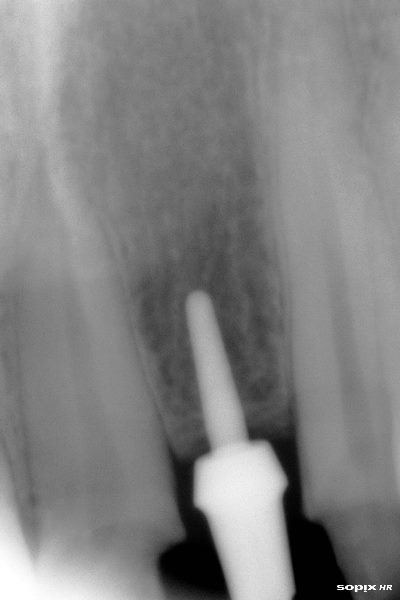

Implante ONE PIECE colocado

Post Image